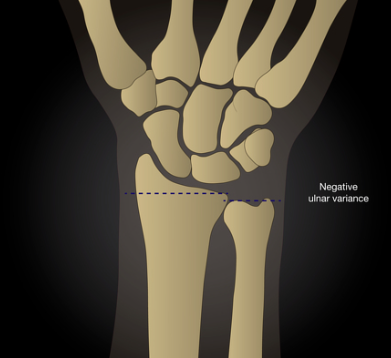

• Ulna minus

• Forma do semilunar → menor e triangular→maior susceptibilidade a desenvolver a doença → classificação de Zapinco

• 80% da das pessoas com doença de Kienbock apresentam ulna minus.

• Verdadeiro

• No RX AP - formato do semilunar → menor e triangular

• No RX AP - altura da ulna → ulna minus